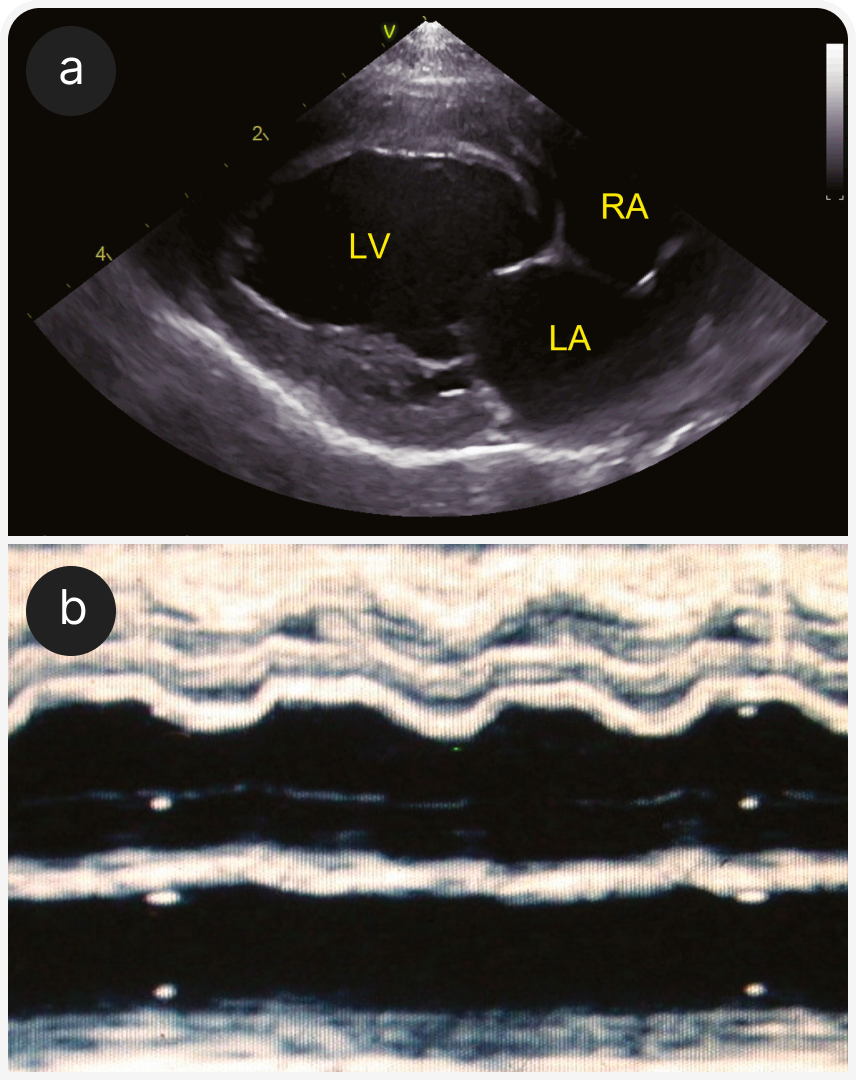

1. Терминальная стадия гипертрофической кардиомиопатии. На сегодняшний день ГКМП — наиболее распространенный тип кардиомиопатии, но на конечных стадиях она может проявляться другими фенотипами. Этот термин используют, если ГКМП отмечена в анамнезе, даже если при обследовании не выявлена сегментарная или генерализованная гипертрофия левого желудочка или выявлена очень легкая гипертрофия. Левый желудочек может быть гипокинетичным или расширенным (Рисунок 2), может быть виден инфаркт миокарда (Рисунок 3).

(b) М-режим; ЛЖ с нарушением систолической функции у той же кошки, что и на рисунке 6а; фракционное укорочение было низким, а движение свободной стенки правого желудочка субъективно хорошим.